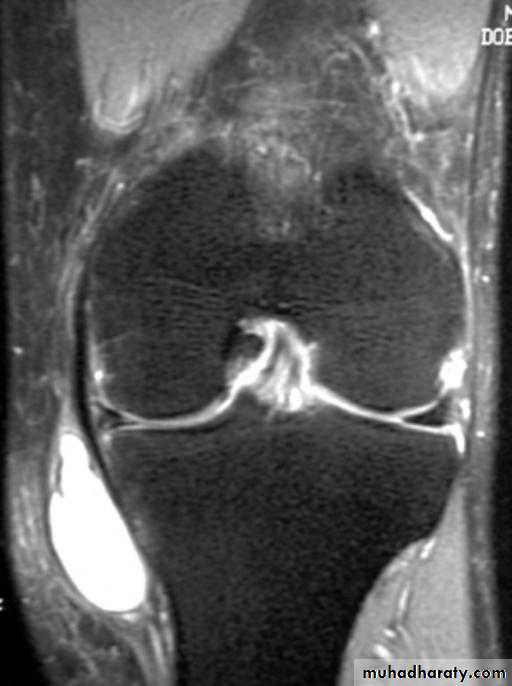

• X-ray; to exclude associated fracture.

• Arthroscopy; it’s the best to give direct visualization of the inside of the joint to prove the diagnosis & exclude other possible injuries.

• MRI; good and accurate noninvasive technique specially if associated with arthroscopic findings.